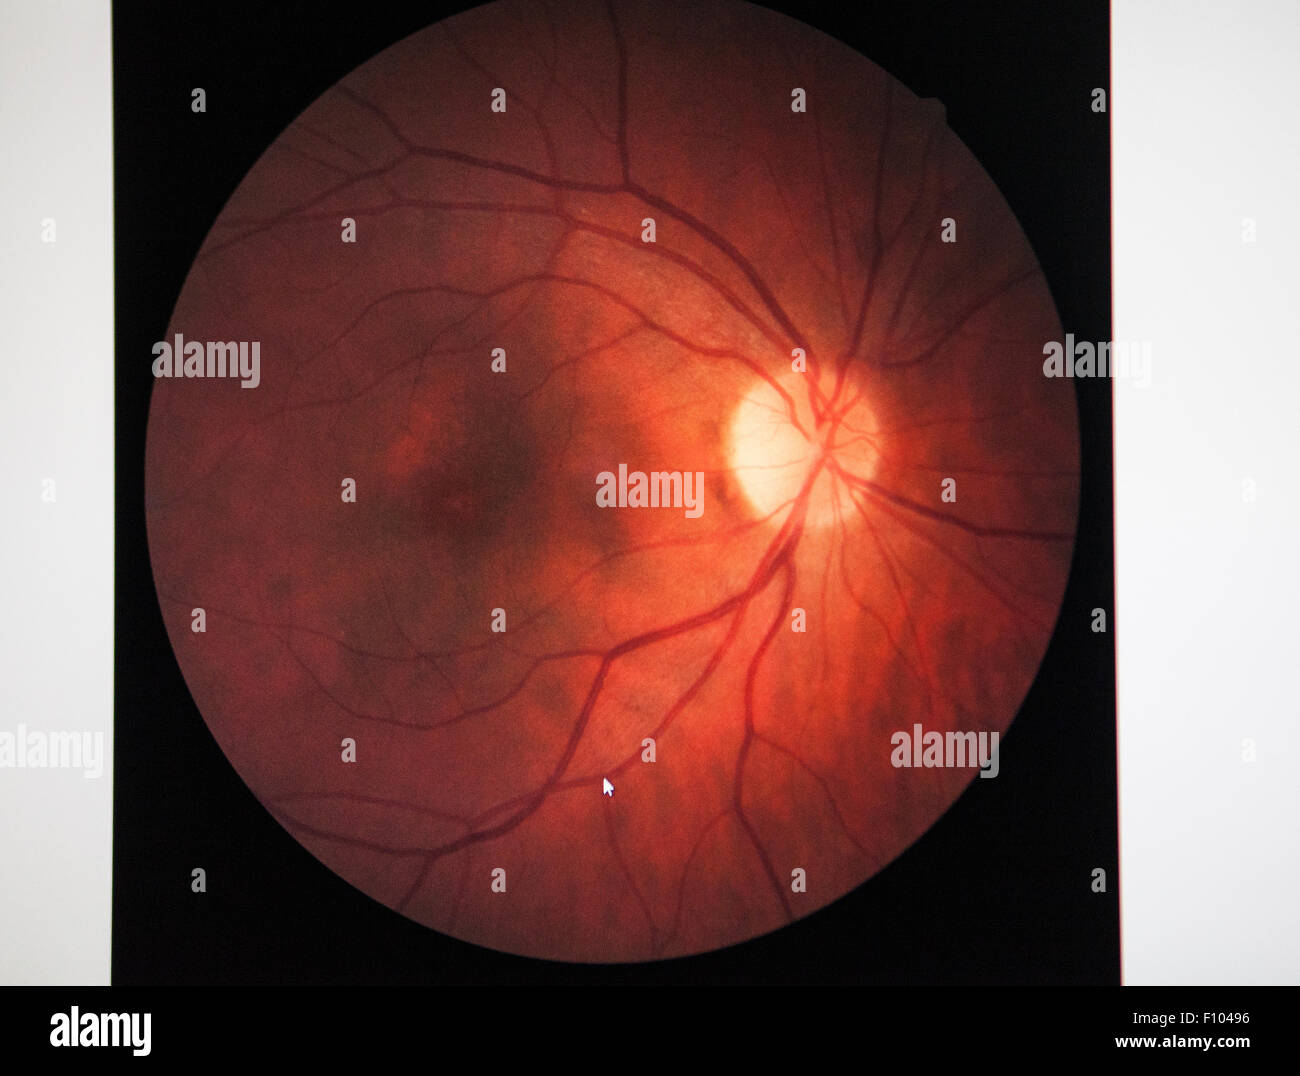

RETINAL EDEMA Stock Photohttps://www.alamy.com/image-license-details/?v=1https://www.alamy.com/stock-photo-retinal-edema-86669890.html

RETINAL EDEMA Stock Photohttps://www.alamy.com/image-license-details/?v=1https://www.alamy.com/stock-photo-retinal-edema-86669890.htmlRMF10496–RETINAL EDEMA